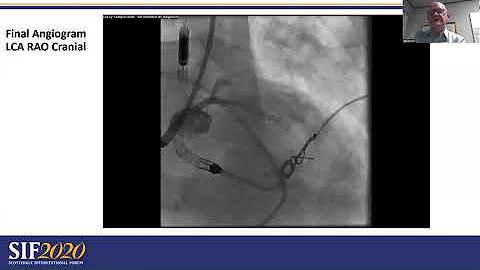

Lc #3 - Unprotected Lm Pci, Impella Assistance - Ccc 2019